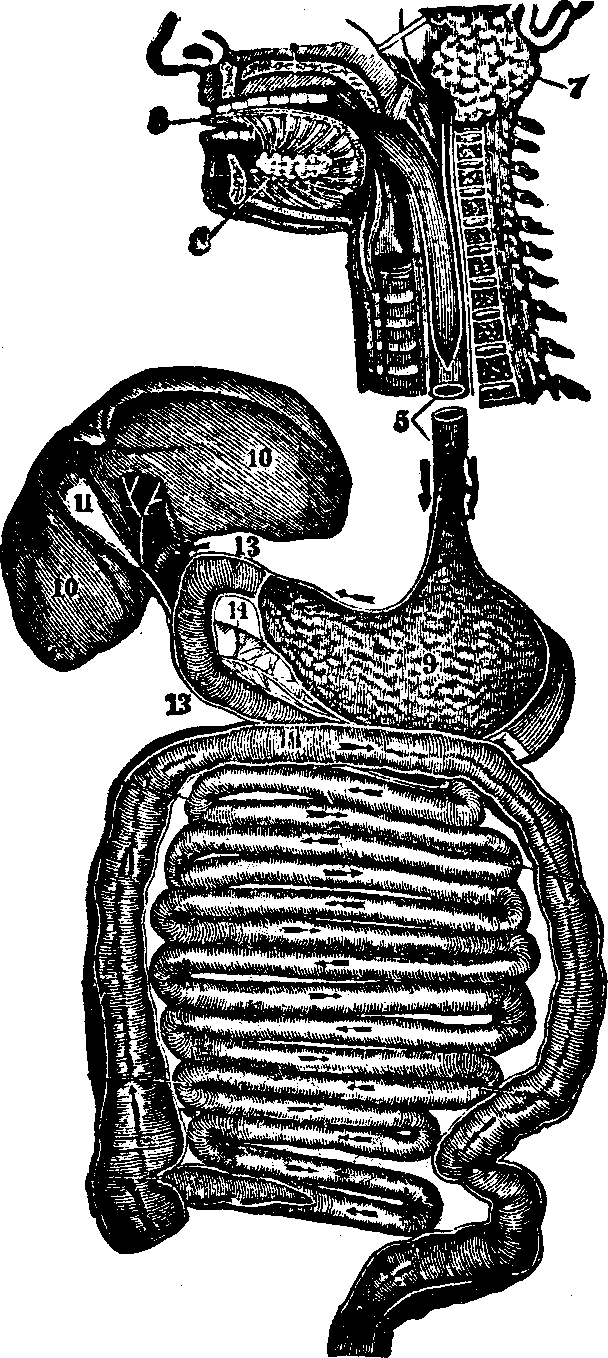

[pg 37]Digestion signifies the act of separating or distributing, hence its application to the process by which food is made available for nutritive purposes. The organs of digestion are the Mouth, Teeth, Tongue, Salivary Glands, Pharynx, Esophagus, the Stomach and the Intestines, with their glands, the Liver, Pancreas, Lacteals, and the Thoracic Duct.

The Pharynx is nearly four inches in length, formed of muscular and membranous cells, and situated between the base of the cranium and the esophagus, in front of the spinal column. It is narrow at the upper part, distended in the middle, contracting again at its junction with the esophagus. The pharynx communicates with the nose, mouth, larynx, and esophagus.

The Esophagus, a cylindrical organ, is a continuation of the pharynx, and extends through the diaphragm to the stomach. It has three coats: first, the muscular, consisting of an exterior layer of fibers running longitudinally, and an interior layer of transverse fibers; second, the cellular, which is interposed between the muscular and the mucous coat; third, the mucous membrane, or internal coat, which is continuous with the mucous lining of the pharynx.

Fig. 28. A representation of the

interior of the stomach. 1. The esophagus. 2. Cardiac orifice

opening into the stomach. 6. The middle or muscular coat. 7.

The interior or mucous coat. 10. The beginning of the duodenum.

11. The pyloric orifice.

The Stomach is a musculo-membranous, conoidal sac, communicating with the esophagus by means of the cardiac orifice (see Fig. 28). It is situated obliquely with reference to the body, its base lying at the left side, while the apex is directed toward the right side. The stomach is between the liver and spleen, subjacent to the diaphragm, and communicates with the intestinal canal by the pyloric orifice. It has three coats. The peritoneal, or external coat is composed of compact, cellular tissue, woven into a thin, serous membrane, and assists in keeping the stomach in place. The middle coat is formed of three layers of muscular fibers: in the first, the fibres run [pg 40]longitudinally; in the second, in a circular direction; and in the third, they are placed obliquely to the others. The interior, or mucous coat, lines this organ. The stomach has a soft, spongy appearance, and, when not distended, lies in folds. During life, it is ordinarily of a pinkish color. It is provided with numerous small glands, which secrete the gastric fluid necessary for the digestion of food. The lining membrane, when divested of mucus, has a wrinkled appearance. The arteries, veins, and lymphatics, of the stomach are numerous.

Fig. 29. Small and large intestines. 1, 1, 2, 2. Small intestine.

3. Its termination in the large intestine. 4. Appendix

vermiformis. 5. Cæcum. 6. Ascending colon. 7.

Transverse colon. 8. Descending colon. 9. Sigmoid flexure of

colon. 10. Rectum.

The Intestines are those convoluted portions of the alimentary canal into which the food is received after being partially digested, and in which the separation and absorption of the nutritive materials and the removal of the residue take place. The coats of the intestines are analogous to those of the stomach, and are, in fact, only extensions of them. For convenience of description, the intestines may be divided into the small and the large. The small intestine is from twenty to twenty-five feet in length, and consists of the Duodenum, Jejunum, and Ileum. The Duodenum, so called because its length is equal to the breadth of twelve fingers, is the first division of the small intestine. If the mucous membrane of the duodenum be examined, it will be found thrown into numerous folds, which are called valvulæ conniventes, the chief function of which appears to be to retard the course of the alimentary matter, and afford a larger surface for the accommodation of the absorbent vessels. Numerous villi, minute thread-like projections, will be [pg 41]found scattered over the surface of these folds, set side by side, like the pile of velvet. Each villus contains a net-work of blood-vessels, and a lacteal tube, into which the ducts from the liver and pancreas open, and pour their secretions to assist in the conversion of the chyme into chyle. The Jejunum, so named because it is usually found empty after death, is a continuation of the duodenum, and is that portion of the alimentary canal in which the absorption of nutritive matter is chiefly effected. The Ileum, which signifies something rolled up, is the longest division of the small intestine. Although somewhat thinner in texture than the jejunum, yet the difference is scarcely perceptible. The large intestine is about five feet in length, and is divided into the Cæcum, Colon, and Rectum. The Cæcum is about three inches in length. Between the large and the small intestine is a valve, which prevents the return of excrementitious matter that has passed into the large intestine. There is attached to the cæcum an appendage about the size of a goose-quill, and three inches in length, termed the appendix vermiformis. The Colon is that part of the large intestine which extends from the cæcum to the rectum, and which is divided into three parts, distinguished as the ascending, the transverse, and the descending.

The Thoracic Duct is the principal trunk of the absorbent system, and the canal through which much of the chyle and lymph is conveyed to the blood. It begins by a convergence and union of the lymphatics on the lumbar vertebræ, in front of the spinal column, then passes upward through the diaphragm to the lower part of the neck, thence curves forward and downward, opening into the subclavian vein near its junction with the left jugular vein, which leads to the heart.

Fig. 32. c, c.

Right and left subclavian veins. b. Inferior vena cava. a.

Intestines. d. Entrance of the thoracic duct into the left

subclavian vein. 4. Mesenteric glands, through which the lacteals

pass to the thoracic duct.

Fig. 33. The inferior surface of the liver. 1. Right lobe. 2.

Left lobe. 3. Gall-bladder.

The Liver, which is the largest gland in the body, weighs [pg 43]about four pounds in the adult, and is located chiefly on the right side, immediately below the diaphragm. It is a single organ, of a dark red color, its upper surface being convex, while the lower is concave. It has two large lobes, the right being nearly four times as large as the left. The liver has two coats, the serous, which is a complete investment, with the exception of the diaphragmatic border, and the depression for the gall-bladder, and which helps to suspend and retain the organ in position; and the fibrous, which is the inner coat of the liver, and forms sheaths for the blood-vessels and excretory ducts. The liver is abundantly supplied with arteries, veins, nerves, and lymphatics. Unlike the other glands of the human body, it receives two kinds of blood; the arterial for its nourishment, and the venous, from which it secretes the bile. In the lower surface of the liver is lodged the gall-bladder, a membranous sac, or reservoir, for the bile. This fluid is not absolutely necessary to the digestion of food, since this process is effected by other secretions, nor does bile exert any special action upon, starchy or oleaginous substances, when mixed with them at a temperature of 100° F. Experiments also show that in some animals there is a constant flow of bile, even when no food has been taken, and there is consequently no digestion to be performed. Since the bile is formed from the venous blood, and taken from the waste and disintegration of animal tissue, it would appear that it is chiefly an excrementitious fluid. It does not seem to have accomplished its function when discharged from the liver and poured into the intestine, for there it undergoes various alterations previous to re-absorption, produced by its contact with the intestinal juices. Thus the bile, after being [pg 44]transformed in the intestines, re-enters the blood under a new form, and is carried to some other part of the system to perform its mission.

The Spleen is oval, smooth, convex on its external, and irregularly concave on its internal, surface. It is situated on the left side, in contact with the diaphragm and stomach. It is of a dark red color, slightly tinged with blue at its edges. Some physiologists affirm that no organ receives a greater quantity of blood, according to its size, than the spleen. The structure of the spleen and that of the mesenteric glands are similar, although the former is provided with a scanty supply of lymphatic vessels, and the chyle does not pass through it, as through the mesenteric glands. The Pancreas lies behind the stomach, and extends transversely across the spinal column to the right of the spleen. It is of a pale, pinkish color, and its secretion is analogous to that of the salivary glands; hence it has been called the Abdominal Salivary Gland.

Fig.

34. Digestive organs. 3. The tongue. 7. Parotid gland.

8. Sublingual gland. 5. Esophagus. 9. Stomach.

10. Liver. 11. Gall-bladder, 14. Pancreas. 13,

13. The duodenum. The small and large intestines are represented below

the stomach.